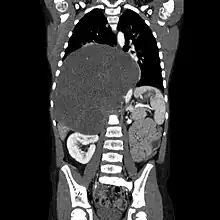

CT scan of a large ganglioneuroma within the chest cavity

Ganglioneuromas most frequently occur in the abdomen, however these tumors can grow anywhere sympathetic nervous tissue is found. Other common locations include the adrenal gland, paraspinal retroperitoneum, posterior mediastinum, head, and neck.[1] It is contained within the neuroblastic tumors group, which includes:[3] Ganglioneuroma (benign), Ganglioneuroblastoma (intermediate), Neuroblastoma (aggressive).

Ganglioneuromas can be diagnosed visually by a CT scan, MRI scan, or an ultrasound of the head, abdomen, or pelvis. Blood and urine tests may be done to determine if the tumor is secreting hormones or other circulating chemicals. A biopsy of the tumor may be required to confirm the diagnosis.[4]